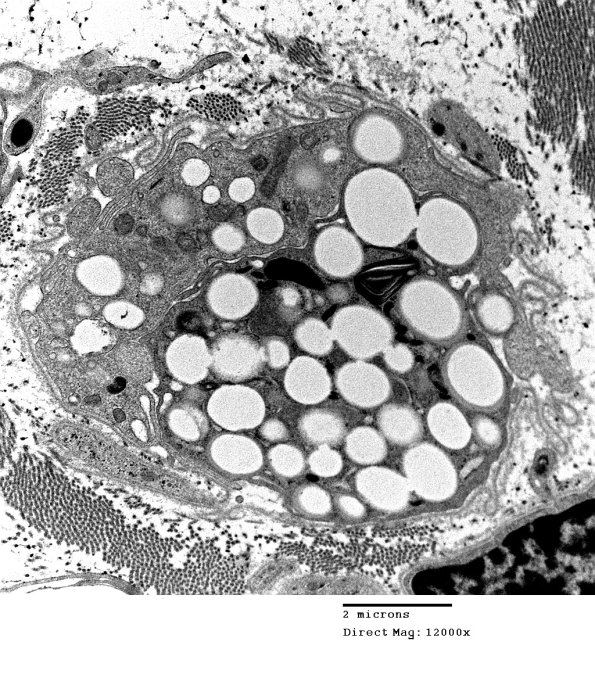

A similar macrophage within the original Schwann cell basement membrane.